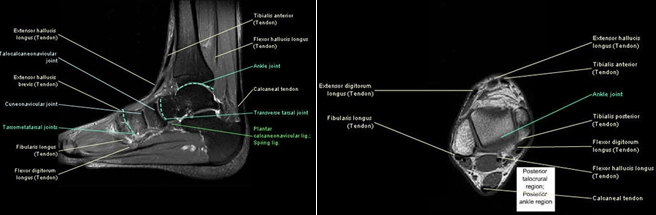

Normal Magnetic Resonance Imaging Anatomy Of The Ankle & Foot

ankle anatomy foot mri normal coronal resonance imaging t1 magnetic fig

MRI - FOOT

mri atlas

ankle mri radiology joint sectional resonance magnetic